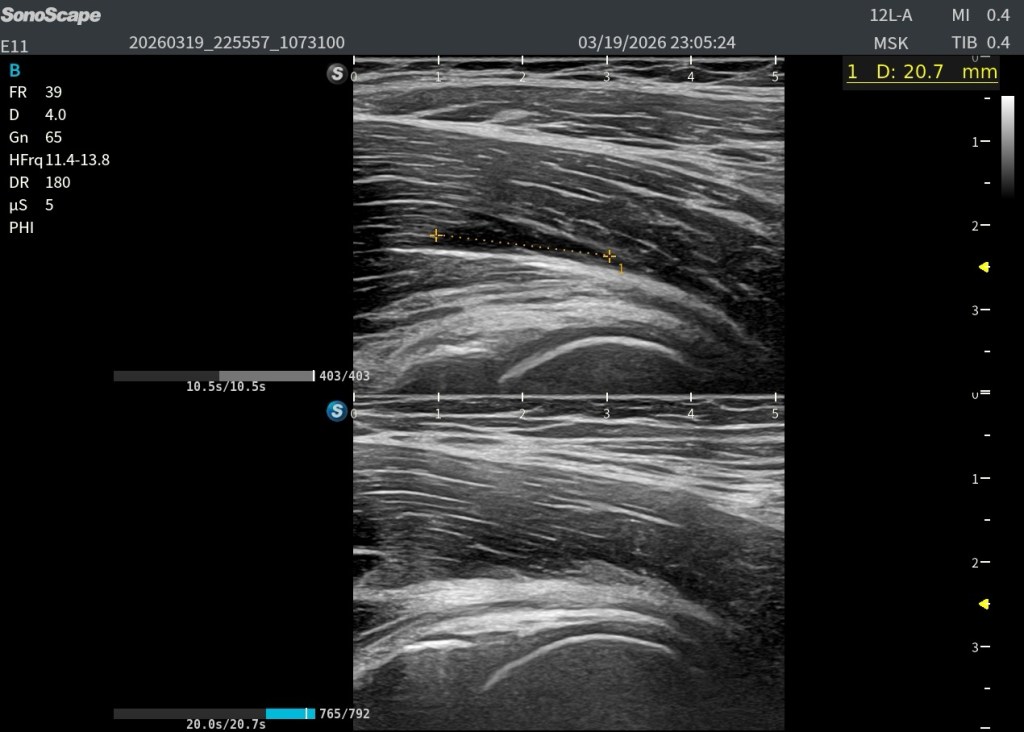

En eje longitudinal (eje largo – línea roja): Imagen anecoica alargada Localizada en las fibras profundas del psoas Con una longitud aproximada de 2,5 cm En eje transversal (eje corto – línea amarilla): La lesión se reproduce claramente, confirmando su existencia siempre en dos ejes. Si no lo veo en 2 cortes, no existe.

Y comparar…eso siempre nos va a dar un plus.

Es fundamental reconocer el patrón normal del músculo:

Músculo → hipoecogénico Fibras con líneas hiperecogénicas alargadas

Por tanto:

👉 La aparición de una imagen anecoica dentro de este patrón fibrilar debe alertarnos inmediatamente de patología muscular, generalmente:

Rotura Hematoma intramuscular

En este caso, la correlación clínica y ecográfica es directa.